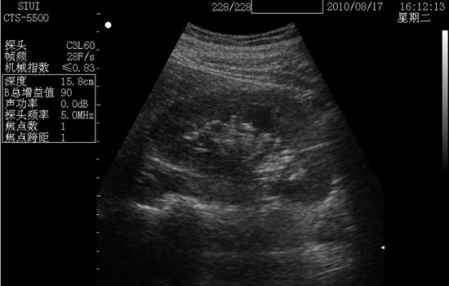

普通b超其实也就是二维的黑白b超。普通b超的应用范围也很广,主要是作用就是观察身体内部结构,比如孕妇胎儿情况、肝脏等部位。用孕妇b超**来说,普通b超是黑白色的,通过b超测出胎儿双顶径、头围和腹围等数据,进一步确认宝宝的预产期,还可帮助医生观察胎儿是否存活或有无畸形,羊水是否过多等。

价格:普通B超价格相对比较便宜,不同地方的医院价格会不一样,但差异基本相差不大,最便宜的有35元,稍贵一点的90元也有。